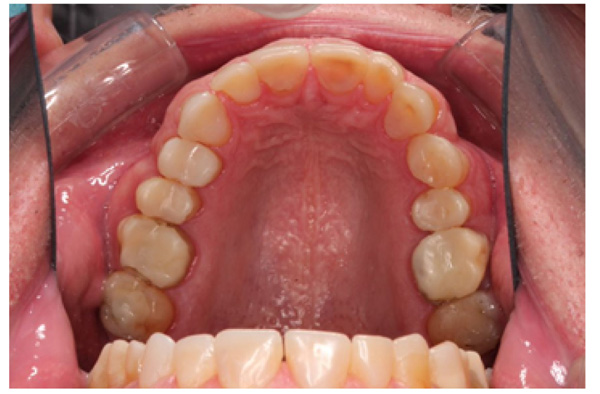

IPS Empress Direct ® (Ivoclar Vivadent, Schaan, Liechtenstein) composite was syringed onto the worn surface and into the stent,which was seated onto the tooth. The composite was cured through the stent for 20 seconds; then the stent was removed, and the composite curing light was used again to ensure afull set for a further 40 seconds. The PTFE tape was removed, the excess composite at the gingival margin was trimmed back with narrow and ultra-fine diamond finishing burs, and a final polish was performed using Shofu Super-Snap Rainbow® discs (Kyoto 605-0983, Japan). The resultsare shown in Figs. (8-10). The slight increase in the vertical dimension is seen when comparing the pre-operative frontal image (Fig. 2) with the post-op image (Fig. 8), where some of the labial surfaces of the lower incisors is now visible, which was planned from the outset.

The occlusal scheme was created using a mutually protected occlusion with canine guidance. The patient was informed of possible transitory problems, including difficulty in eating or speaking and other possible discomforts. He was reassured that adaptation is usually quick. Alower bilaminar (dual-laminate) night guardof 3mm thickness was provided in order toprotect the composites during bruxism [14]. He was followed up for 4 months after completion of all the restorations to find out at which time he had adapted perfectly well and was functioning normally. He waspleased with the esthetic result but was warned that composites could get stained by foods and drinks such as tea, coffee, and curry (mainly turmeric). However, he was reassured that the surface stain was easily polished off.